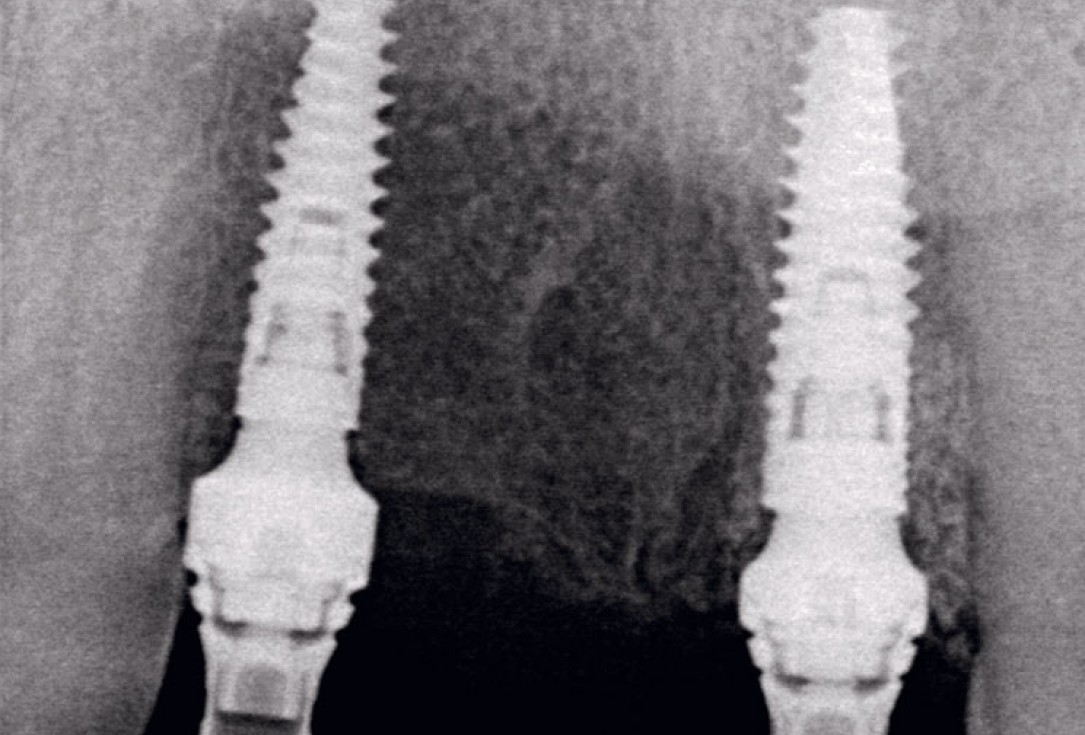

16/17 - Radiographic control.

Socket preservation using cerabone® and Straumann® Emdogain® - Dr. S. Pelekanos